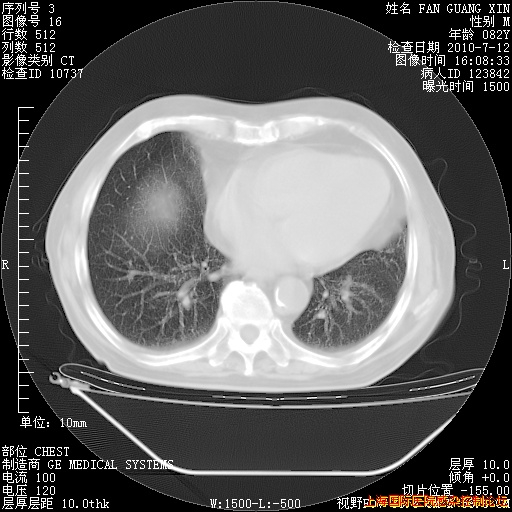

今天CT

整整相隔30天的肺部CT好像有所好转啊。甲强龙减量第3天,需要观察体温。

海管,自昨日你和我通完话后,不知您岳父消化道症状有无缓解?体温怎样?阅读7.12日胸部ct,个人认为目前激素治疗是有效的,甲强龙减量是适宜的。因在抗痨治疗,需密切观察肝功、肾功能和血常规。不过,老年、长期住院和大量使用激素,很担心菌群失调发生